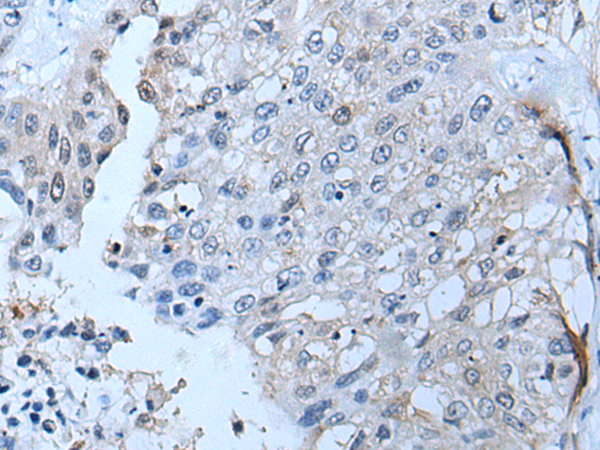

The image is immunohistochemistry of paraffin-embedded Human liver cancer tissue using P07246(TNFRSF10C Antibody) at dilution 1/30. (Original magnification: ×200) |

The image is immunohistochemistry of paraffin-embedded Human lung cancer tissue using P07246(TNFRSF10C Antibody) at dilution 1/30. (Original magnification: ×200) |